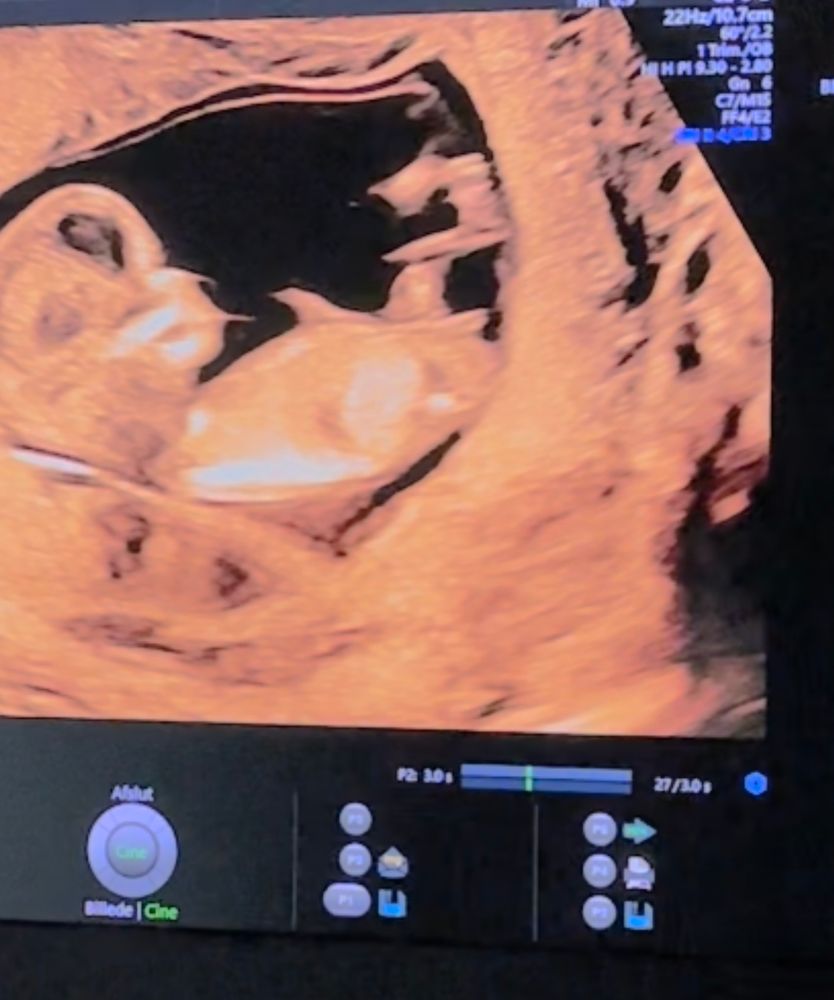

УЗИ 12 недель 😍

УЗИ, КТГ, доплерПривет всем! Сегодня ходила на первый скрининг 💕 здоровенькие и все хорошо 🙏❤️

Не могу разобраться где у малыша половой бугорок, я так понимаю он скрестил ноги. И периодически прыгал. Но есть скриншоты с видео.

Публикую для голосования, кто там 😅❤️